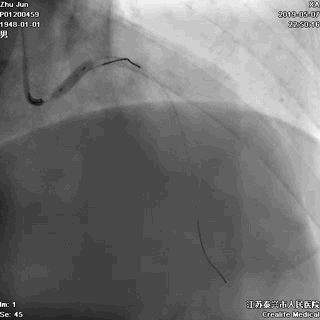

一、指引导管到位

---防止导管嵌顿和深插

主干开口病变,指引导管嵌顿或深插,就可能一招致命

游离一根导丝至升主动脉,防止导管深插

轻轻冒烟,证实指引导管到位

轻轻冒烟,大致了解前降支的情况

这一步相当重要。否则,无论是导管嵌顿,还是导管深插,稍不留意患者都有可能一招致命。